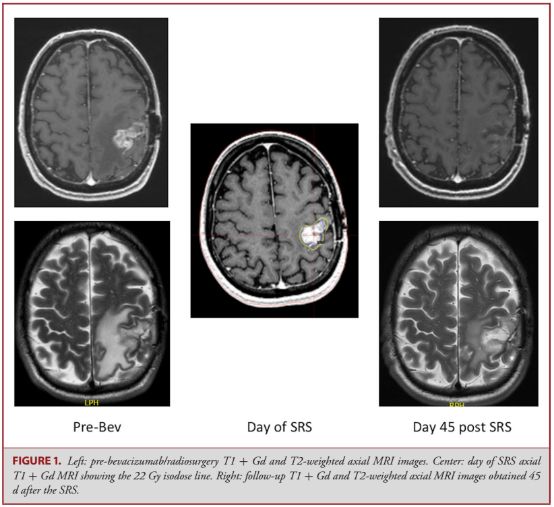

17. 增加放射剂量+贝伐珠单抗治疗复发性/进展性胶质母细胞瘤的临床I期研究

Phase I Trial of Radiosurgery Dose Escalation Plus Bevacizumab in Patients With Recurrent/Progressive Glioblastoma.

PMID: 28973311 DOI: 10.1093/neuros/nyx369

立体定向放射外科(SRS)对复发性胶质母细胞瘤(rGBM)的有效性仍不确定,且SRS与胶质瘤中放射性坏死的高风险有关。该研究是一项前瞻性临床I期试验,通过在SRS之前给予单剂量的贝伐单抗并持续至进展,以确定使用贝伐珠单抗治疗rGBM 的高剂量SRS的安全性和两者的协同益处。。

共有7例男性和2例女性参加了这项研究,结果显示,在SRS之前使用贝伐珠单抗治疗,能够使患者病灶体积在SRS治疗(剂量从18Gy-22Gy不等)当天明显缩小(从平均4.7cm3降至2.86cm3),且无一例患者出现与SRS治疗相关的副作用。SRS+贝伐珠单抗联合应用下,有3例患者出现部分反应,6例患者病情稳定。所有患者中位生存期和总生存期分别为7.5和13个月。

因而作者认为,在SRS之前使用贝伐珠单抗治疗的患者,其放射安全剂量可递增至22Gy剂量的,尚需更多研究来证实贝伐珠单抗治疗后SRS对rGBM的疗效。

![]()